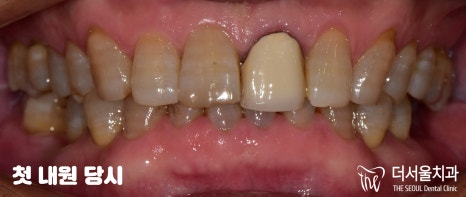

『수정구 태평동 치과 첫 내원』

우선 구강 상태를 확인한 결과,

36, 37, 36번 어금니를 상실했으며

47번 치아는 신경치료를 받아야 되는 상황이라

두 가지 진료를 받아야 되었습니다.